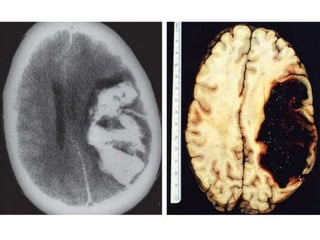

Imagenes

• Atrofia cerebral

simetrica .

• Baja atenuación de

sustancia blanca

en region

periventricular.

• Surco y venticulos prominentes que muestran la atrofia generalizada y

simetrica.

• No efecto masa.

Imagenes • Atrofia cerebral simetrica . • Baja atenuación de sustancia blanca en region periventricular.

• Surco yventiculos prominentes que muestran la atrofia generalizada y simetrica. • No efecto masa.